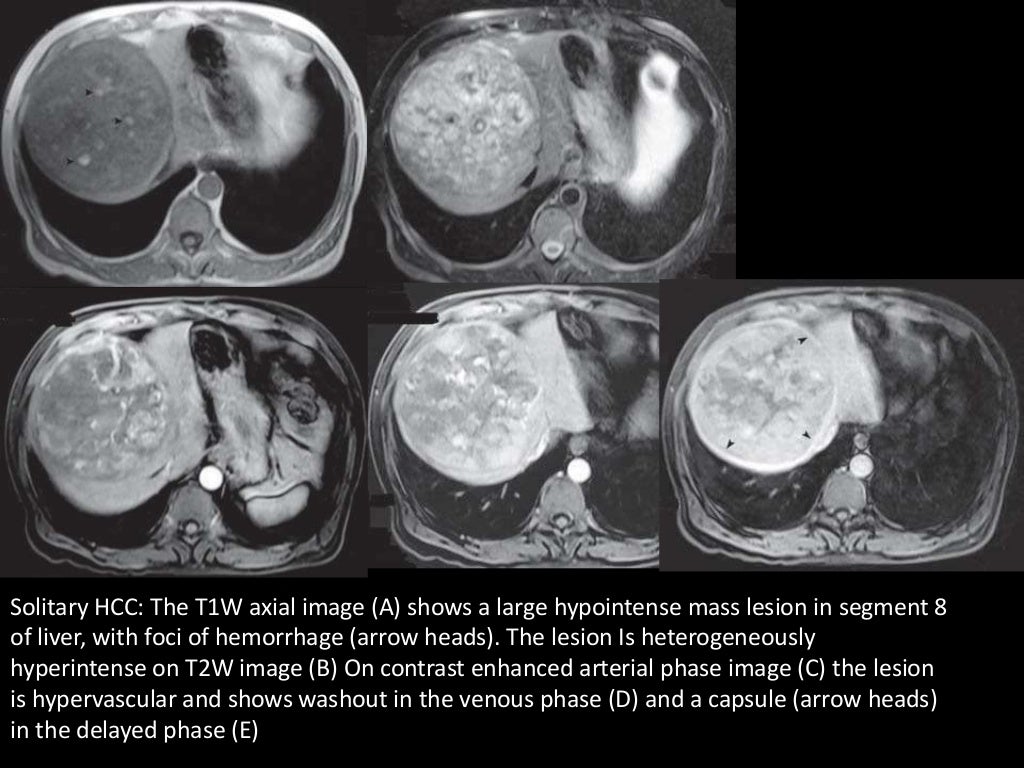

Imaging of Malignant Liver Lesions What Is Malignant Neoplasm Of Hepatic Flexure — by a. — short answer. hepatic flexure cancers are associated with worse survival compared to more proximal colon cancers. — adenosquamous carcinoma (asc) is defined as a very rare subset of colorectal cancer containing both. The hepatic flexure is the bend. Mendelson, md september 21, 2024. — hepatocellular carcinoma (hcc) is the most common. What Is Malignant Neoplasm Of Hepatic Flexure.

From www.researchgate.net